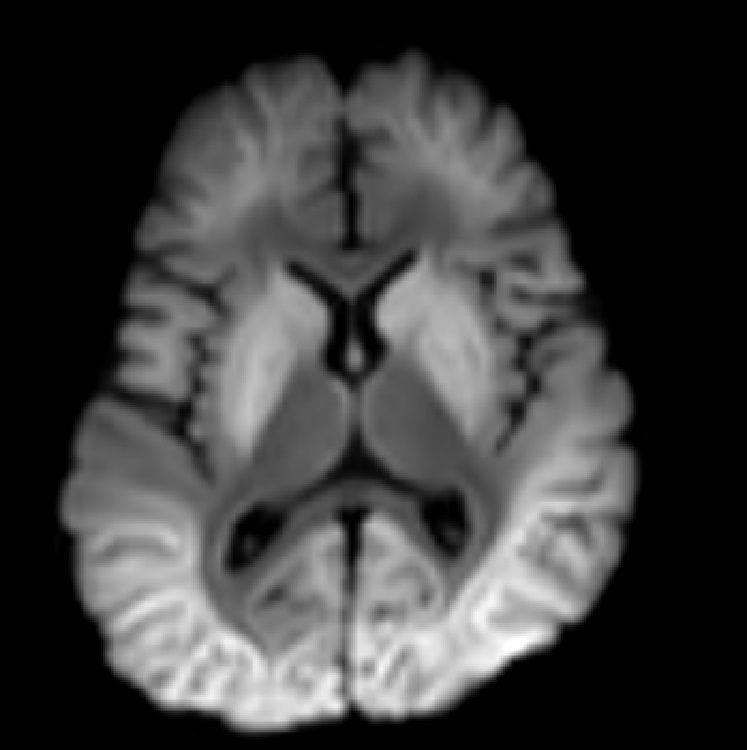

A 3-year-old boy presents with fever, seizures, and other clinical features suggestive of encephalopathy Acute leukoencephalopathy with restricted diffusion (ALERD) Background: Acute leukoencephalopathy with restricted diffusion is a clinical-radiological spectrum characterized by the clinical features of acute encephalopathy and neuroimaging showing diffusion restriction predominantly in the subcortical white matter. Etiologically, it is classified as Infectious ALERD or Toxic ALERD, based on whether it occurs in the setting of infection or toxins, respectively. Clinical Presentation: ALERD presents as acute encephalopathy. Imaging features may not be evident in first 2 to 3 days. They appear at the third to ninth days after symptom onset. Key Diagnostic Features: There are two distinct imaging patterns recognized: diffuse type and central sparing type. In the diffuse type, diffusion restriction is seen involving bilateral subcortical white matter. In the central sparing type, there is sparing of central regions of the brain, mainly the primary sensory motor cortex. The diffusion restriction in subcortical white matter appears similar to multiple dendritic bright tree branches, which is characteristically described as "bright tree appearance." Differential Diagnosis: Atypical PRES and ADEM: Changes are more pronounced on T2/FLAIR than DWI Postictal changes: T2/FLAIR hyperintensities are usually seen in both the cortex and subcortical white matter. Clinical symptoms are transient. Febrile infection-related epilepsy syndrome (FIRES): changes are seen in gray matter structures such as the mesial temporal lobes, basal ganglia, and/or hippocampi Mild leukoencephalopathy with reversible splenial lesion (MERS): Lesions are mainly restricted to the splenium of corpus callosum